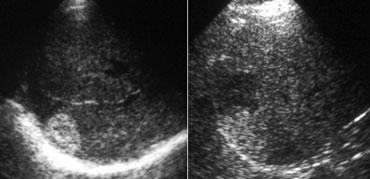

TRÁI: Hình ảnh siêu âm điển hình của u máu. PHẢI: Cũng là u máu nhưng trên nền gan tăng âm, do đó tổn thương tương đối giảm âm. Lưu ý hiện tượng tăng âm phía sau.

Siêu âm

Hầu hết các u máu được phát hiện bằng siêu âm.

Nếu phải chọn một từ để đặc trưng cho u máu trên siêu âm, từ đó có lẽ là ‘tăng âm’.

Tuy nhiên, cần nhận thức rõ rằng điều này đơn giản có nghĩa là tổn thương tăng âm so với nhu mô gan bình thường.

Nếu gan tăng âm do thoái hóa mỡ (steatosis), u máu có thể xuất hiện giảm âm (hình minh họa).

Một đặc điểm quan trọng khác của u máu là hiện tượng tăng âm phía sau.

Điều này là do tổn thương được cấu thành từ các kênh chứa máu.